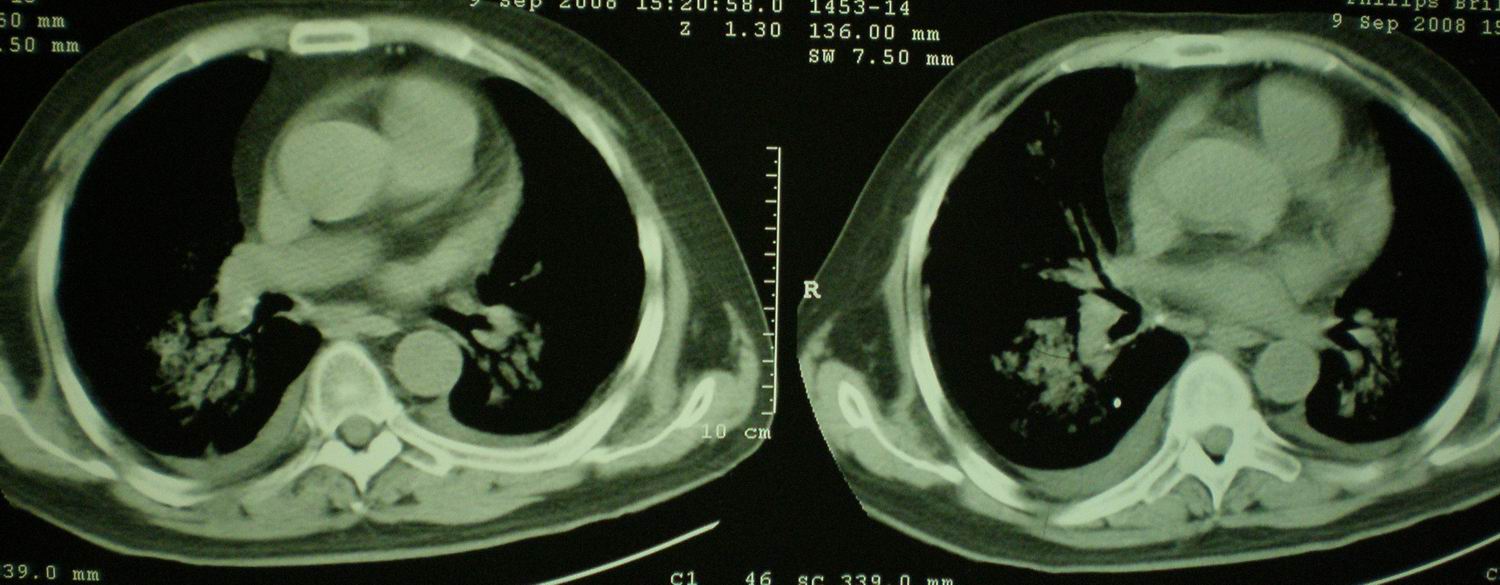

2008年9月8日ct片:

我仔细看了下病人的出院小结,当时情况危急,诊断里有1型呼衰。心包周围的是脂肪密度。结合三次ct扫描的图象分析,个人认为:1、病人目前肺部病灶基本消失,双侧胸腔内少量积液,抗结核治疗才一个多月,就算是结核,抗结核治疗有效果,为何效果如此好,一点纤维灶的痕迹都没有呢,再就是患者做过气管镜检查及活检、痰检均未找到结核的证据。所以不支持结核的诊断。

2、结合现在的ct片,考虑:肺水肿及真菌感染,双侧胸腔积液。

急性呼吸窘迫综合征,肺水肿,与激素减量太快有关.双侧胸腔积液.

机遇性感染。双肺实质满布。且以肺门周围为主。不象结核。